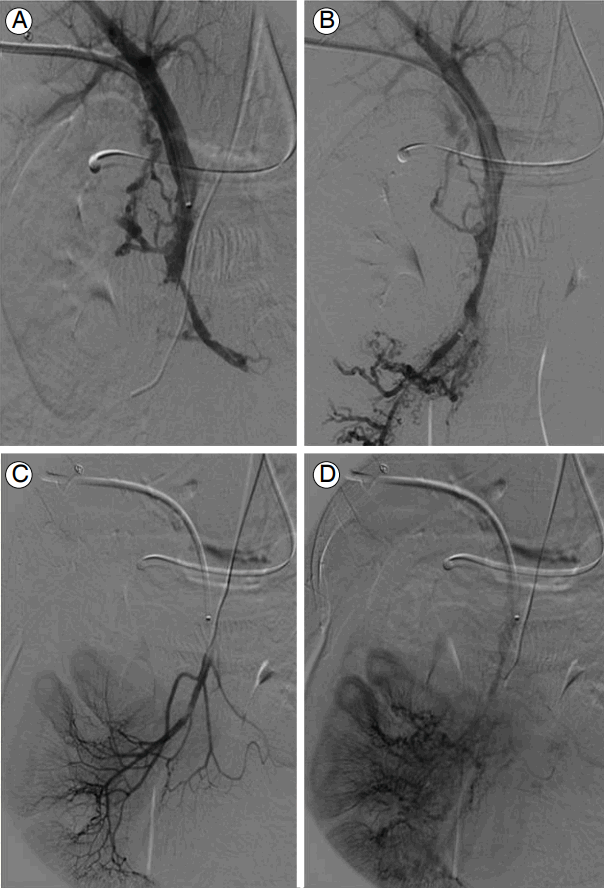

Figure 4.

A filling defect within the SMV is seen on a direct portography through a right hepatic puncture (A). Post aspiration thrombectomy at the SMV; the SMV venogram shows much clearing of the SMV lumen (B). After thrombectomy, SMA angiography showed delayed venous return to the mesenteric venous system (C and D). SMV, superior mesenteric vein.